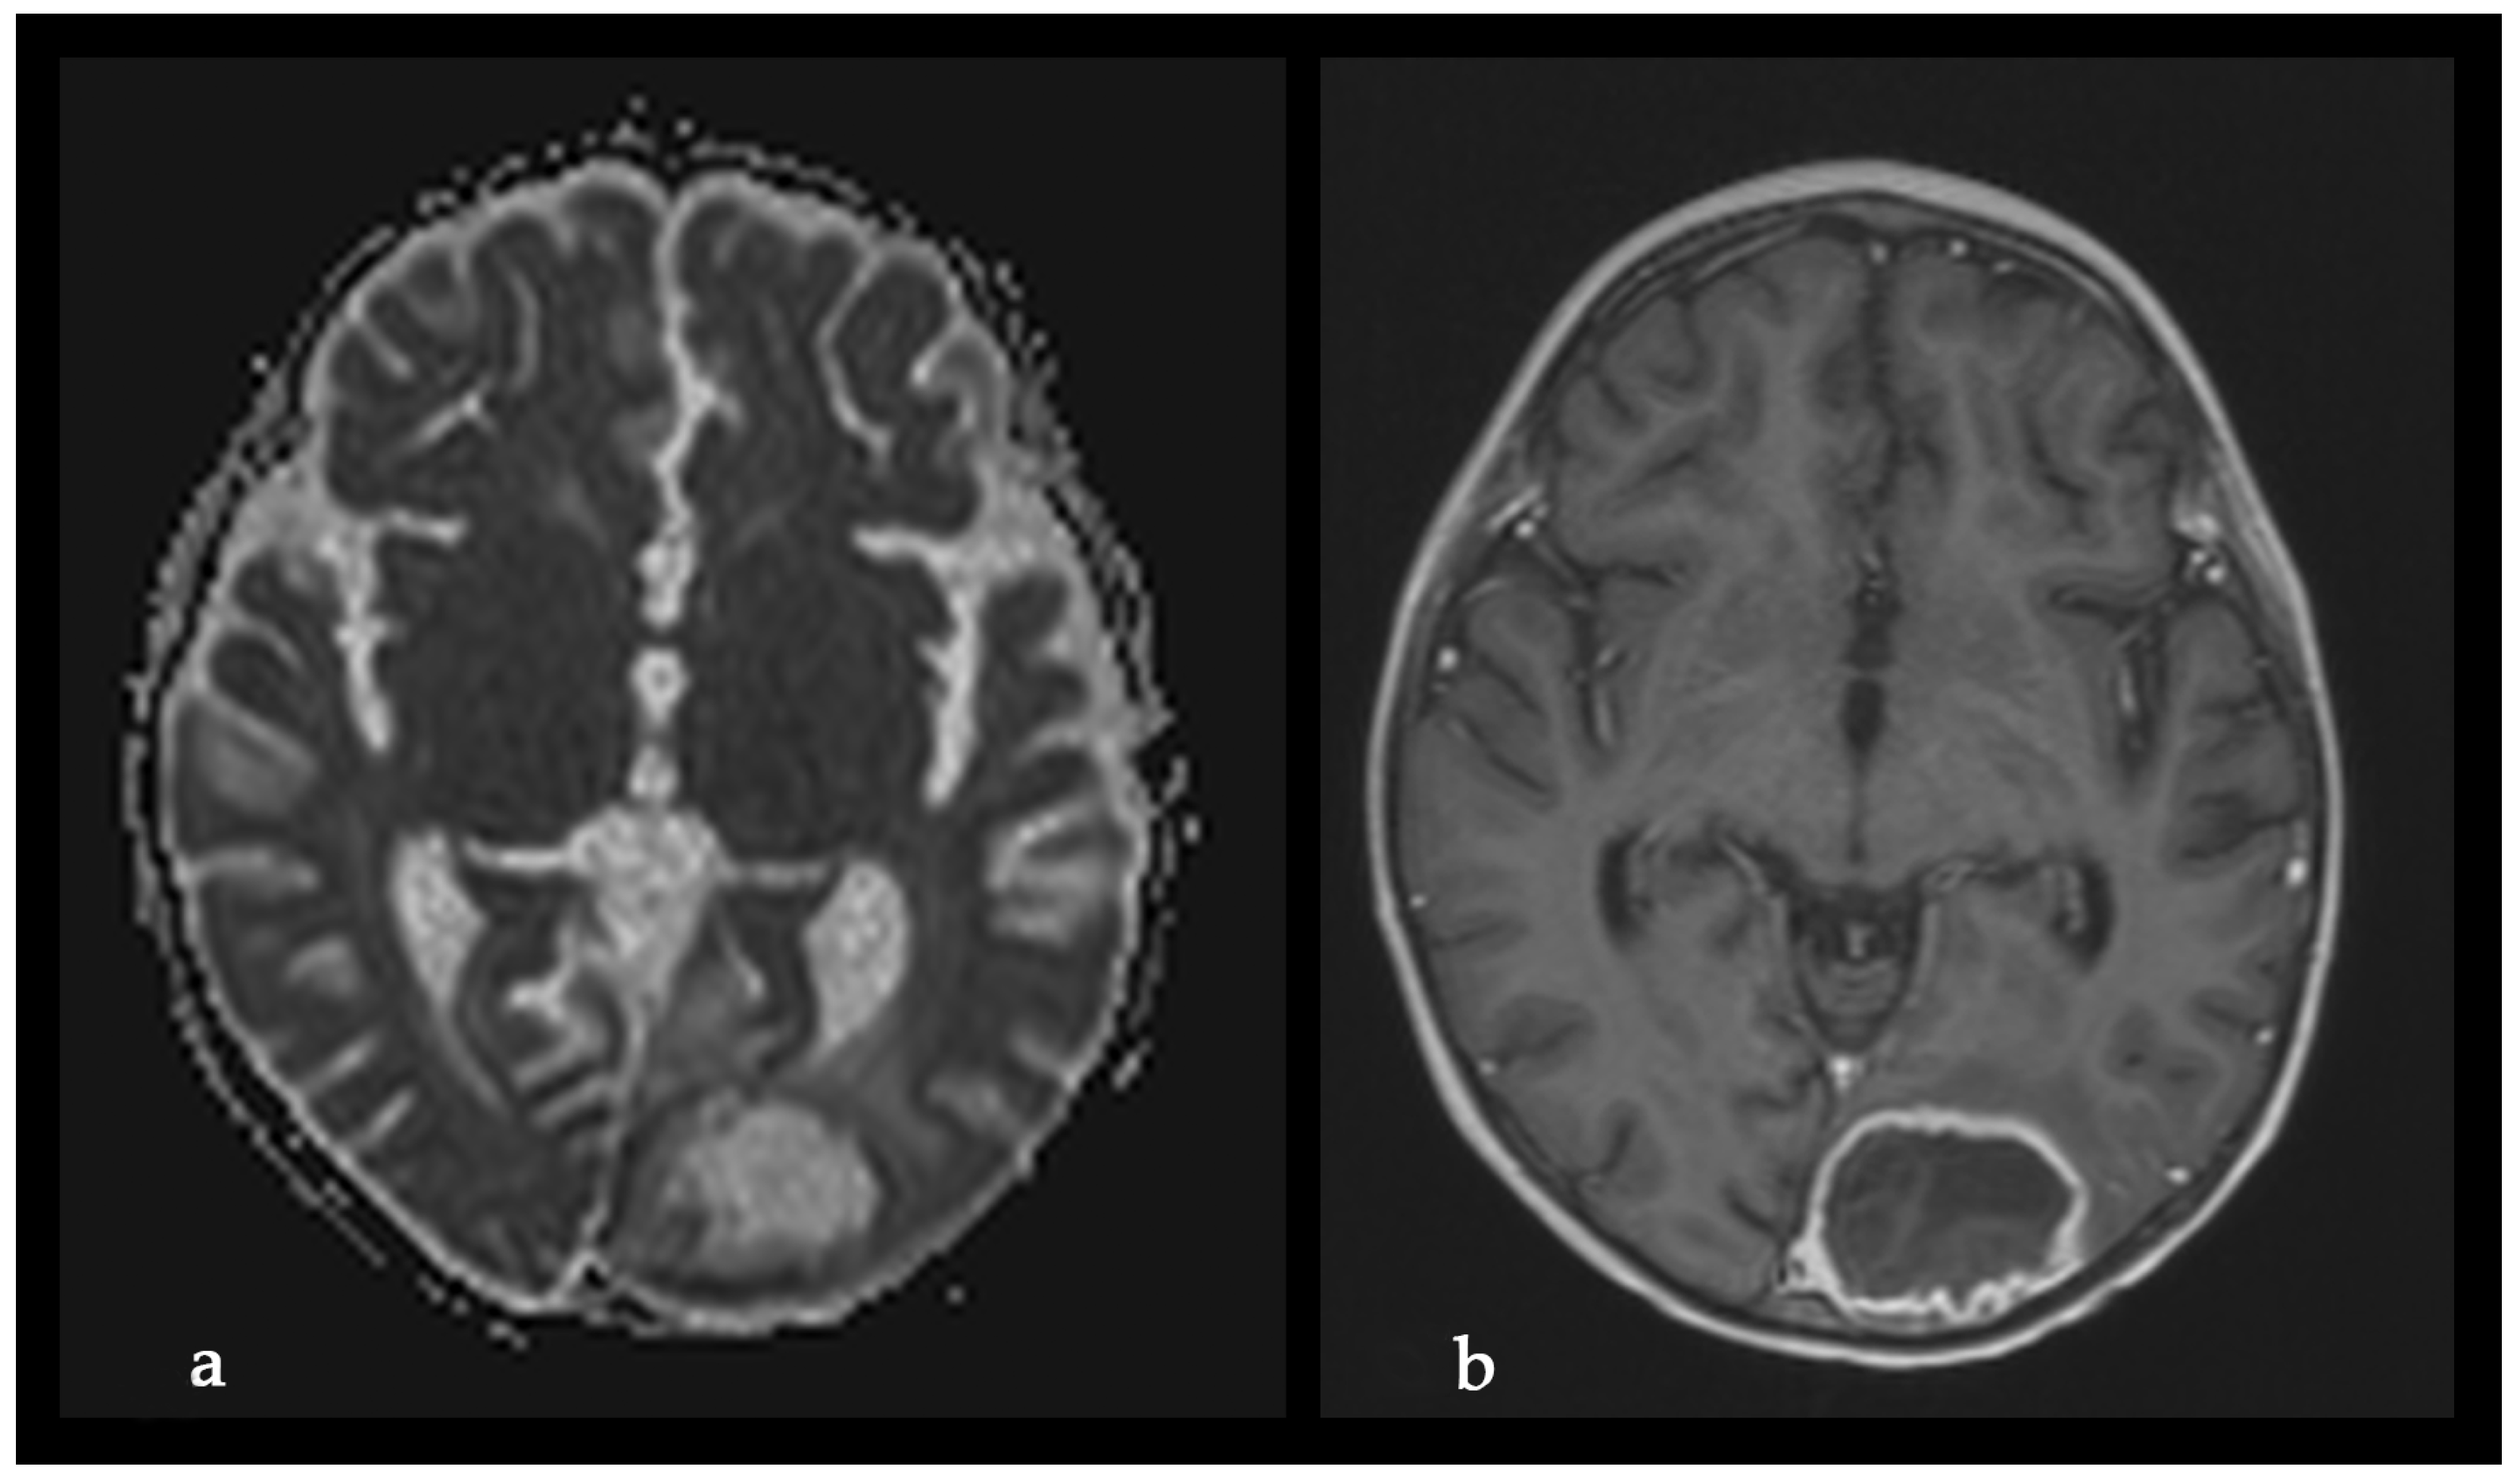

A Rare Case of Rhizomucor pusillus Infection in a 3-Year-Old Child with Acute Lymphoblastic Leukemia, Presenting with Lung and Brain Abscesses—Case Report

Pahnev, Y.; Avramova, B.; Gabrovska, N.; Dontcheva, Y.; Tacheva, G.; Minkin, K.; Kreipe, H.; Yurukova, N.; Penkov, M.; Kartulev, N.; et al. A Rare Case of Rhizomucor pusillus Infection in a 3-Year-Old Child with Acute Lymphoblastic Leukemia, Presenting with Lung and Brain Abscesses—Case Report. Infect. Dis. Rep. 2026, 18, 2. https://doi.org/10.3390/idr18010002